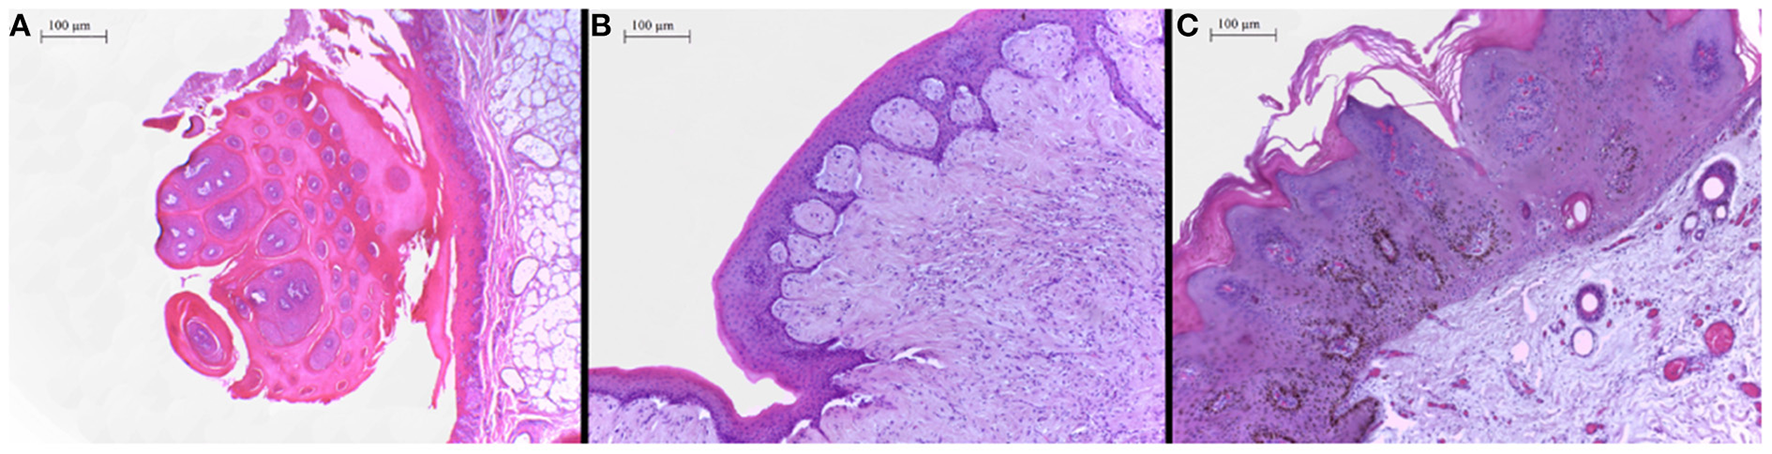

In the histopathological evaluation of the neoplastic lesions with papillomatous aspect located at the esophagus and rumen, a well-differentiated proliferation of stratified squamous epithelial cells was observed. The epithelial cells were disposed in thick layers and formed papilliform projections supported by a thin connective stromal core, occasionally forming a peduncle. The cells exhibited evident desmosomal junctions, occasionally with numerous keratohyalin granules. Into the stratum spinosum of the epithelial proliferation, there were sparse individual or small groups of cells exhibiting cellular degeneration, having a clear cytoplasm and often a condensed nucleus corresponding to koilocytes. These lesions were classified as squamous papillomas (Figure 2A). The smooth-surfaced nodules histologically presented a well-delimited, unencapsulated benign neoplastic proliferation of spindle cells covered by a moderately acanthotic squamous epithelium. The spindle cells were arranged in interlacing streams and bundles supported by moderate collagenous connective stroma. The histological characteristics seen in those nodules are consistent with fibropapillomas (Figure 2B). On the skin, multiple squamous papillomas similar to that of the rumen were also observed (Figure 2C), in addition to multifocal mild lymphoplasmacytic dermatitis, discrete multifocal areas of liquefactive necrosis of the epidermis and moderate hyperkeratosis. The tumoral lesions were classified into squamous papillomas or fibropapillomas according to histopathological characteristics described by Munday et al. (16). There were no other significant histological findings in the remaining tissues.

Figure 2

(A) Proximal esophagus, exophytic proliferation of papillary projections of stratified squamous epithelium forming thick fronds supported by a thin core of fibrovascular stroma converging to a common peduncle. Hematoxylin-eosin (HE) 4×. (B) Ruminal fibropapilloma with neoplastic proliferation of squamous epithelial cells and mesenchymal cells forming streams, expanding the submucosa and elevating the overlying proliferated mucosa. The epithelial component forms numerous acanthomatous projections into the mesenchymal component. Hematoxylin-eosin (HE) 10×. (C) Skin, face, a thick proliferation of squamous epithelial cells is seen forming a broad-based well-delimited nodule with moderate hyperkeratosis.